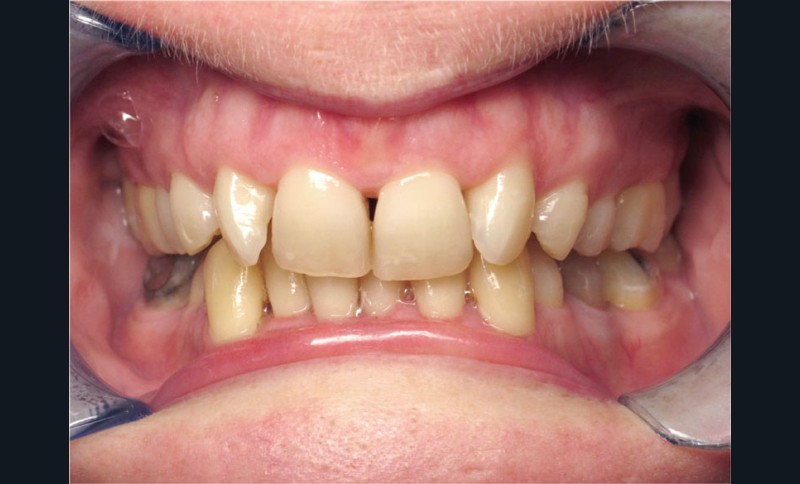

Cas n° 2

Nous lui avons donc proposé un traitement d’alignement avec maintien des 14 et 24 en position de 13 et 23 et optimisation du torque pour favoriser un développement des arcades et chercher à améliorer le sourire et le soutien labial.

La patiente donne son accord pour un appareillage Damon Insignia métal qui permet une individualisation complète des brackets dans les 3 sens de l’espace.

Un appareillage Damon métal a été mis en place, réalisé à partir d’un set up numérique Insignia pour obtenir un contrôle précis des torques et de la forme d’arcade et réduire le temps de finition grâce à un collage indirect très précis.

De larges surélévations postérieures étalées ont été mises en place et la patiente a porté des élastiques précoces suivant les principes de la technique Damon. Les 14 et 24 rempliront le rôle des 13 et 23.

L’objectif, en utilisant la technique Insignia est de réduire le temps de traitement de 28 à 18 mois avec 12 rendez-vous (fig. 5 à 14).